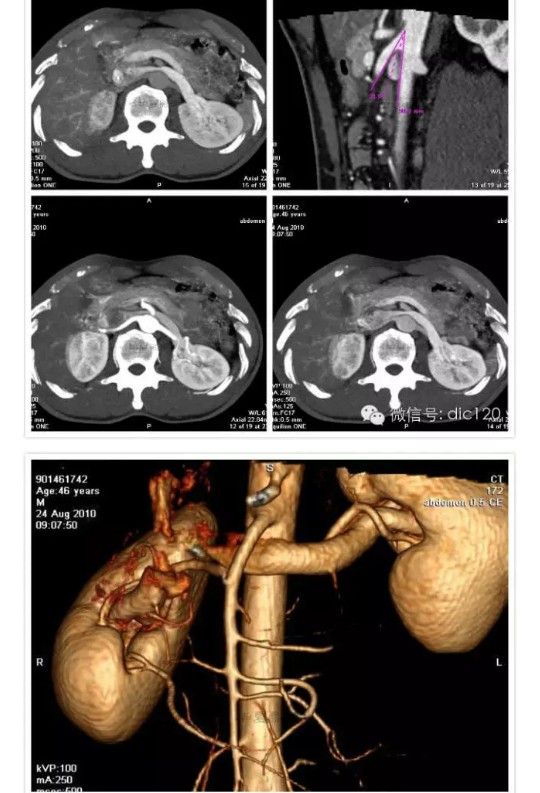

胡桃夹综合征(nutcracker phenomenon)即左肾静脉压迫综合征,又称胡桃夹现象,好发于青春期至40岁左右的男性,儿童发病分布在4~7岁,多发年龄见于13~16岁。 左肾静脉行走在腹主动脉和肠系膜上动脉之间,这两条动脉构成40~60度的夹角,左肾静脉刚好通过此夹角。从解剖上看,右肾静脉径直注入下腔静脉,行程短而直,而左肾静脉需穿过腹主动脉和肠系膜上动脉之间的夹角,跨越腹主动脉前方始能注入下腔静脉,因此左肾静脉远较右肾静脉长。正常时,肠系膜上动脉与腹主动脉之间的夹角被肠系膜、脂肪、淋巴结和腹膜等所充塞,使左肾静脉不致受到压挤。当青春期发育较快、身高迅速增长、脊柱过度伸展、体形急剧变化或肾下垂等情况下,左肾静脉在这个夹角中受到挤压,引起血流变化和相应的临床症状。 胡桃夹现象的主要症状是血尿和蛋白尿,其中无症状肉眼血尿更易发现。血尿的原因是左肾静脉受压致肾静脉高压,左肾静脉扩张所引流的输尿管周围静脉与生殖静脉淤血、与肾集合系统发生异常交通,或部分静脉壁变薄破裂,引起非肾小球性血尿,还会发生睾丸静脉和卵巢静脉淤血而出现肋腹痛,并于立位或行走时加重。另外男性还能发生精索静脉曲张。此外有蛋白尿,不规则月经出血,高血压等。此病的诊断标准为:一侧肾出血;尿红细胞形态为非肾小球性;尿中钙排泄量正常;膀胱镜检查为左侧输尿管口喷血或血性尿;腹部彩超或CT检查可见左肾静脉扩张等。